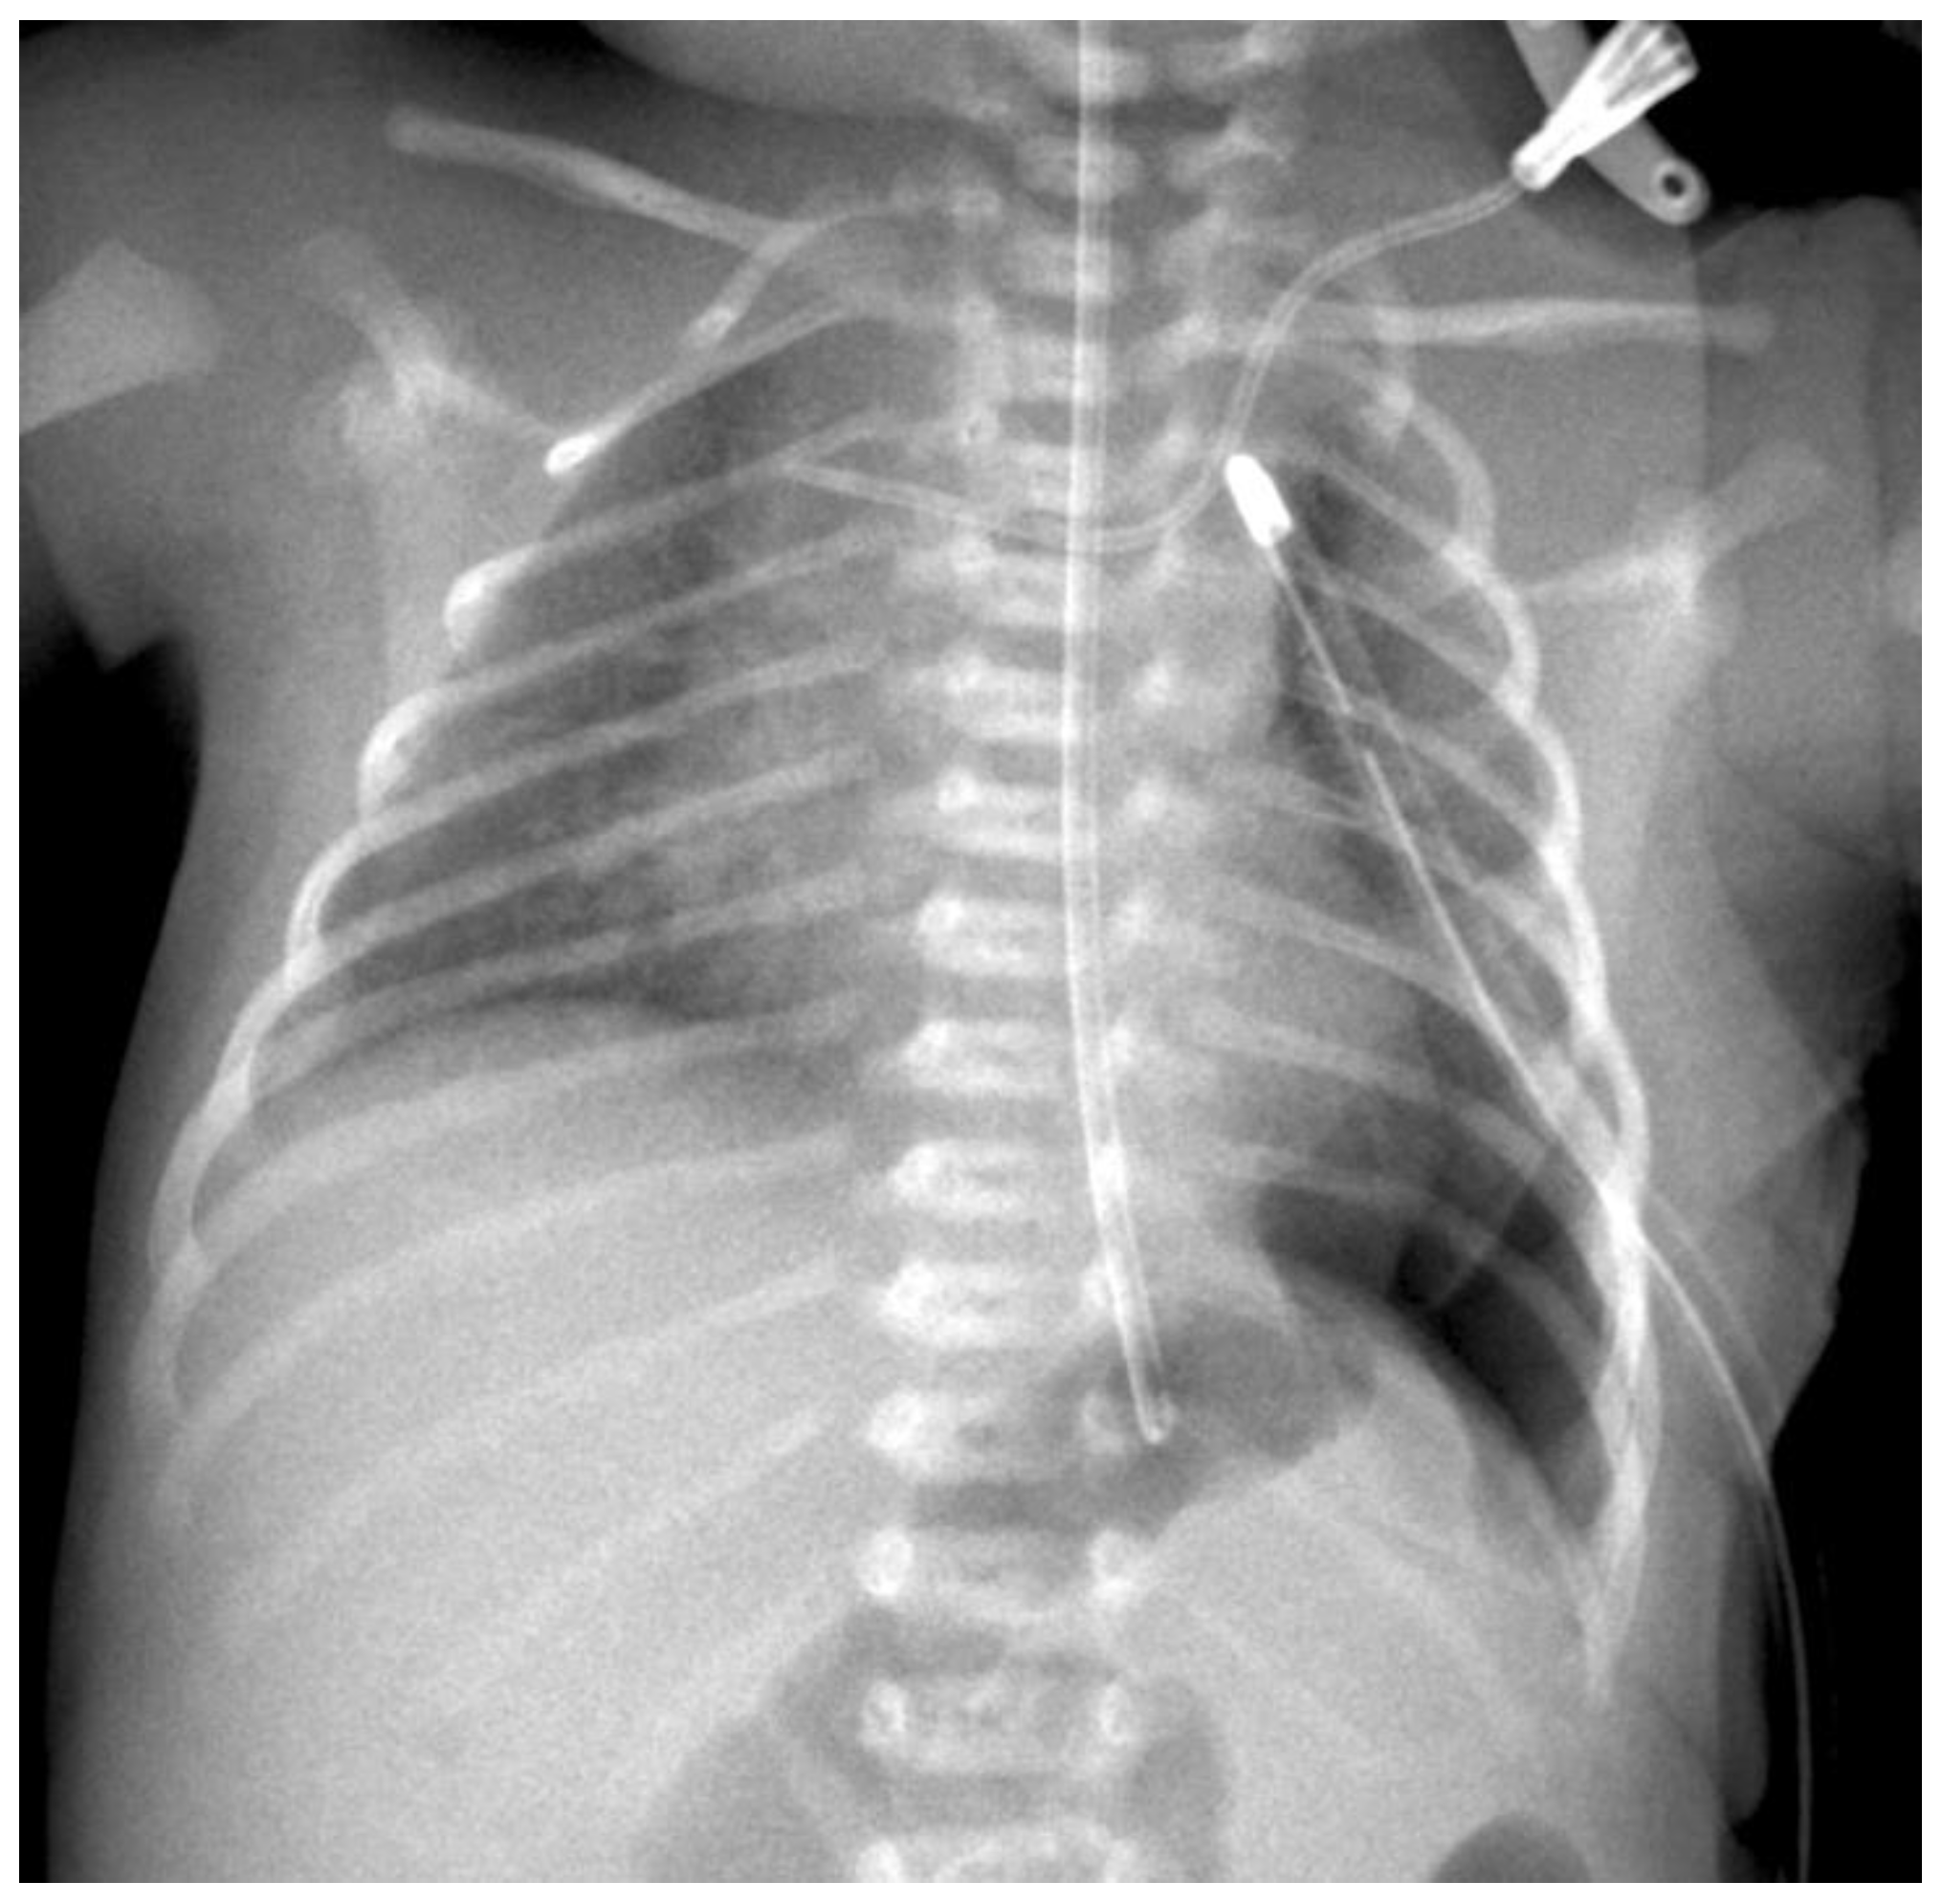

Preoperative Setting: After delivery, a plane X-ray image is taken at the intensive care unit (ICU) (see Figure 1). To rule out other associated anomalies, echocardiography and ultrasound of the brain and the abdominal organs are necessary. All patients were intubated between the first 2–4 h after birth in general to prevent abdominal distension and to avoid an additional compromise of the lung function. As soon as the patient is in a stable cardiorespiratory condition the surgical repair of the defect is performed. The patient is placed on the OR table in lateral decubitus position, the side of the defect upwards with an axillary roll underneath it, and the body is appropriately padded. The preoperative antiseptic routine is performed. Under complete relaxation by anesthesia three 3-mm trocars are placed in the standard location for CDH repair: one at the lower tip of the scapula for the camera, one in the frontal axillary line and one in the posterior. Insufflation pressures during operations are 3–6 mmHg with a flow of 1 L/min. Single lung ventilation is not needed. The herniated bowel is placed downwards into the abdomen and the size and nature of the defect are evaluated.

Figure 1. Preoperative radiograph of a left-sided CDH. The * indicates the intrathoracic bowel.